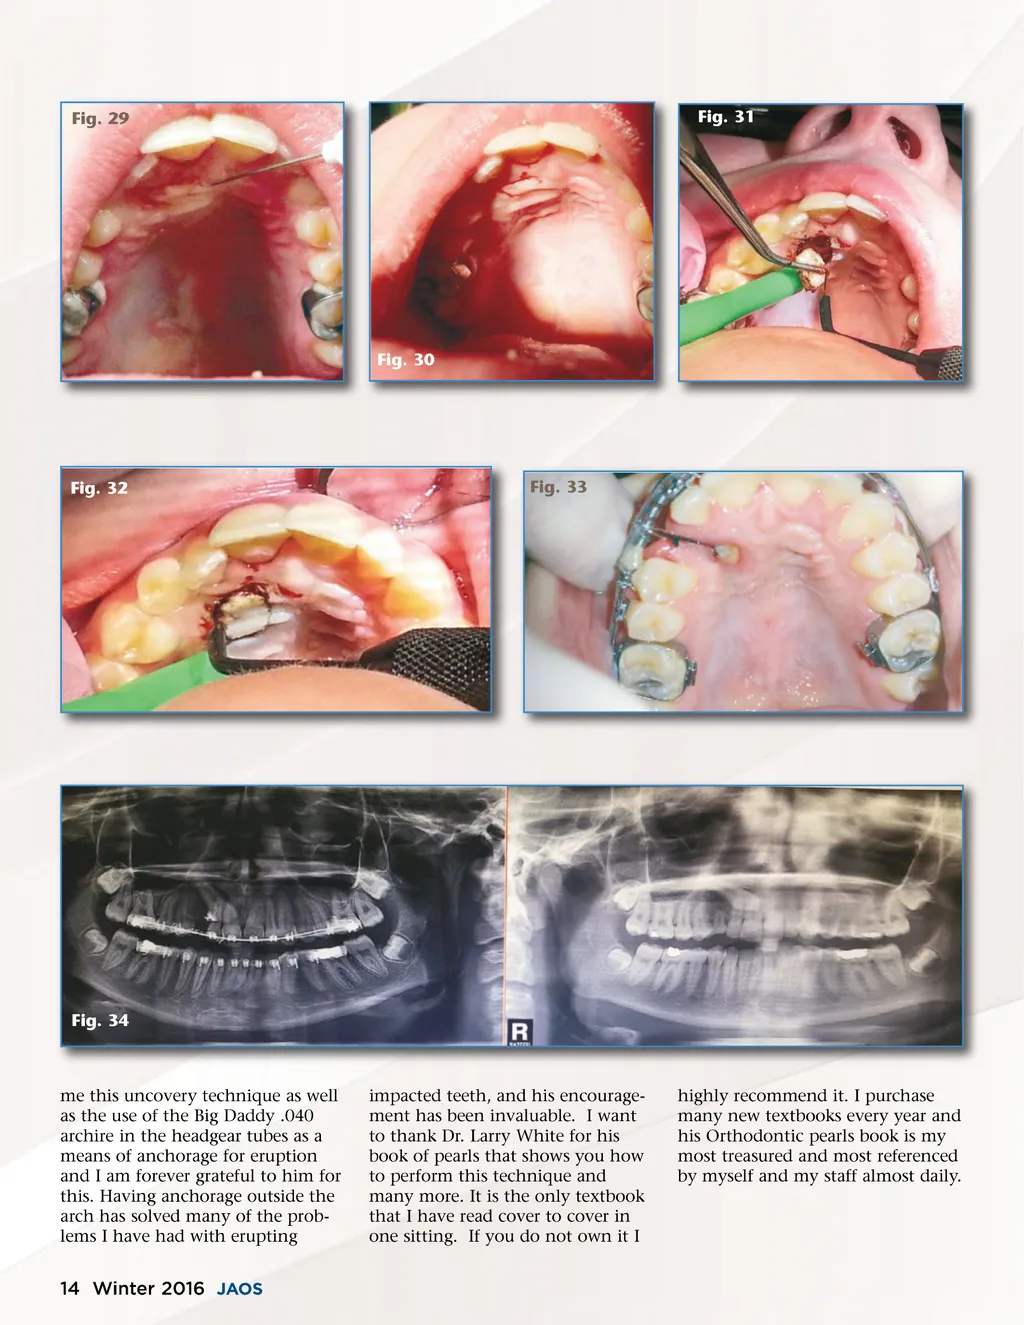

Fig. 29 Fig. 31 Fig. 30 Fig. 32 Fig. 33 Fig. 34 me this uncovery technique as well as the use of the Big Daddy .040 archire in the headgear tubes as a means of anchorage for eruption and I am forever grateful to him for this. Having anchorage outside the arch has solved many of the prob-lems I have had with erupting impacted teeth, and his encourage-ment has been invaluable. I want to thank Dr. Larry White for his book of pearls that shows you how to perform this technique and many more. It is the only textbook that I have read cover to cover in one sitting. If you do not own it I highly recommend it. I purchase many new textbooks every year and his Orthodontic pearls book is my most treasured and most referenced by myself and my staff almost daily. 14 Winter 2016 JAOS